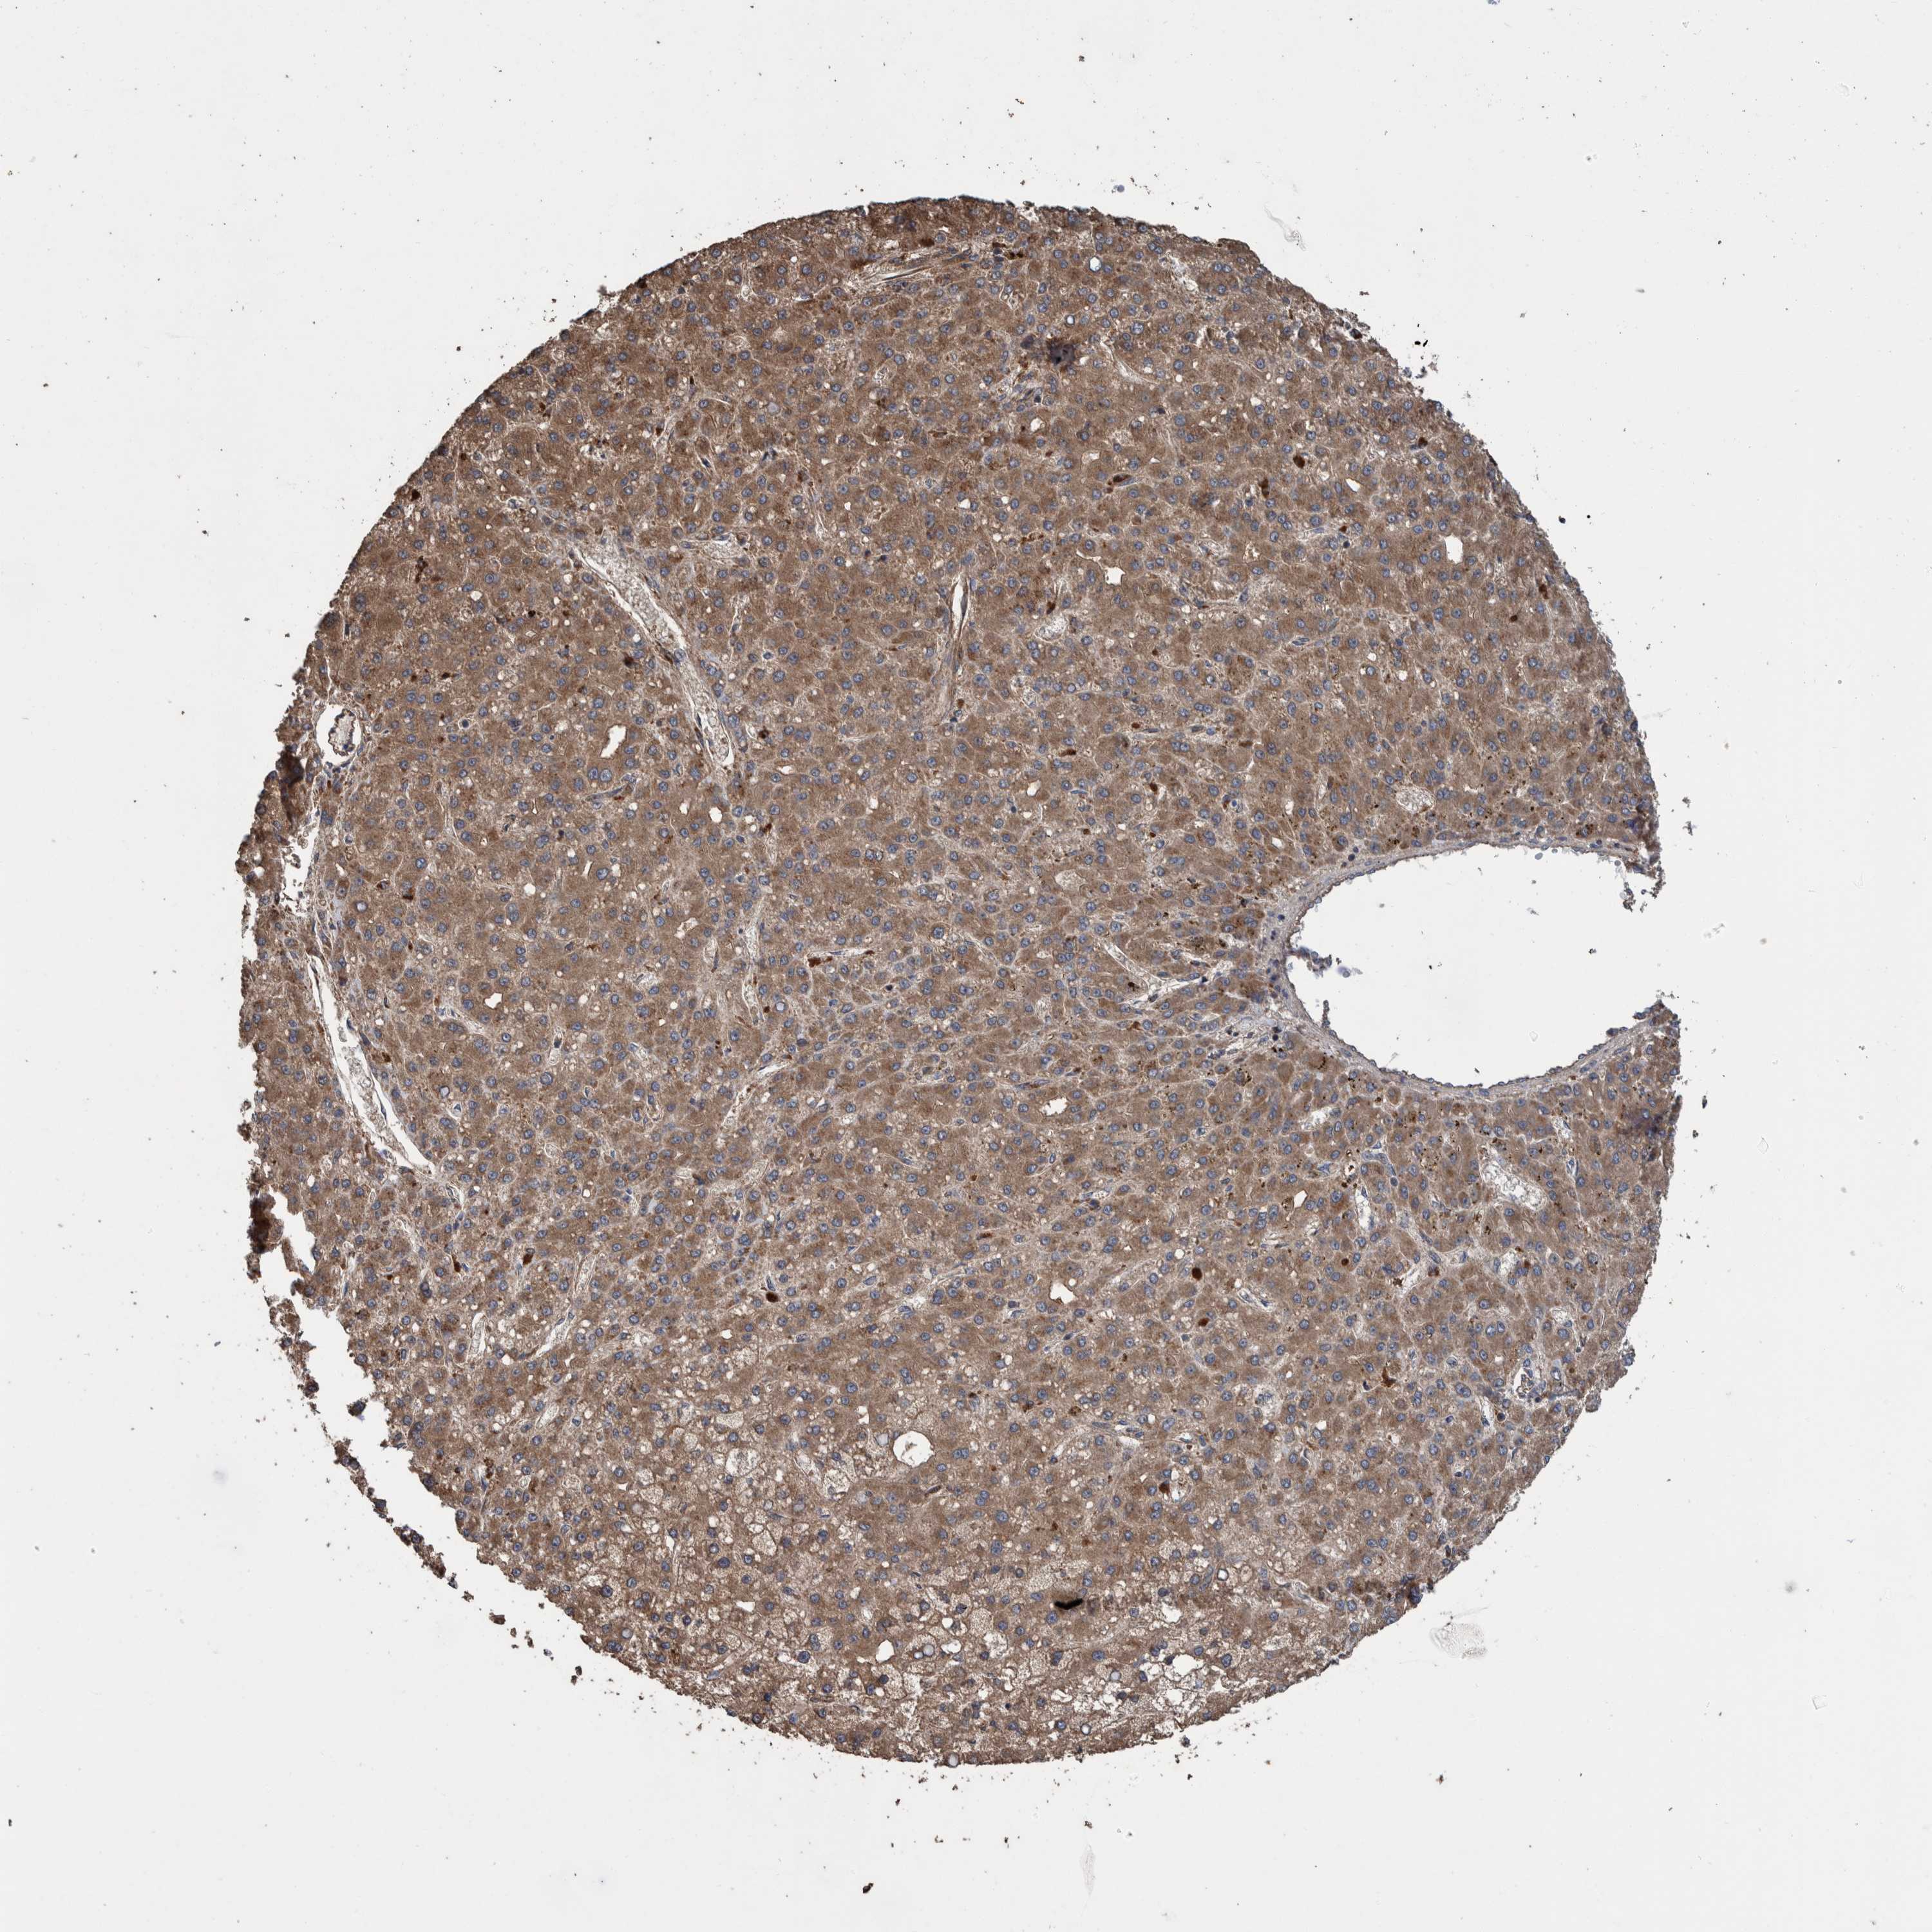

LIVER CANCER - Protein expressioni

A mouse-over function shows sample information and annotation data. Click on an image to view it in a full screen mode. Samples can be filtered based on level of antibody staining by selecting one or several of the following categories: high, medium, low and not detected. The assay and annotation is described here.

Note that samples used for immunohistochemistry by the Human Protein Atlas do not correspond to samples in the TCGA dataset.

Antibody stainingi

Antibody staining in the annotated cell types in the current human tissue is reported as not detected, low, medium, or high, based on conventional immunohistochemistry profiling in selected tissues. This score is based on the combination of the staining intensity and fraction of stained cells.

Each image is clickable and will lead to virtual microscopy that enables deeper exploration of all samples and also displays staining intensity scores, fraction scores and subcellular localization as well as patient and tissue information for each sample.

Antibody HPA023623

Antibody HPA066431

Staining

High

Medium

Low

Not detected

Intensity

Strong

Moderate

Weak

Negative

Quantity

>75%

75%-25%

<25%

None

Location

Nuclear

Cytoplasmic/membranous

Cytoplasmic/membranous,nuclear

Cholangiocarcinoma

Carcinoma, Hepatocellular, NOS